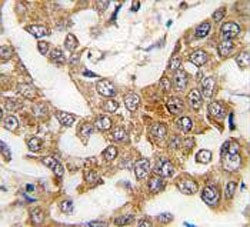

IHC testing of FFPE human breast cancer tissue with Bcl-W antibody. HIER: steam section in pH6 citrate buffer for 20 min and allow to cool prior to staining.